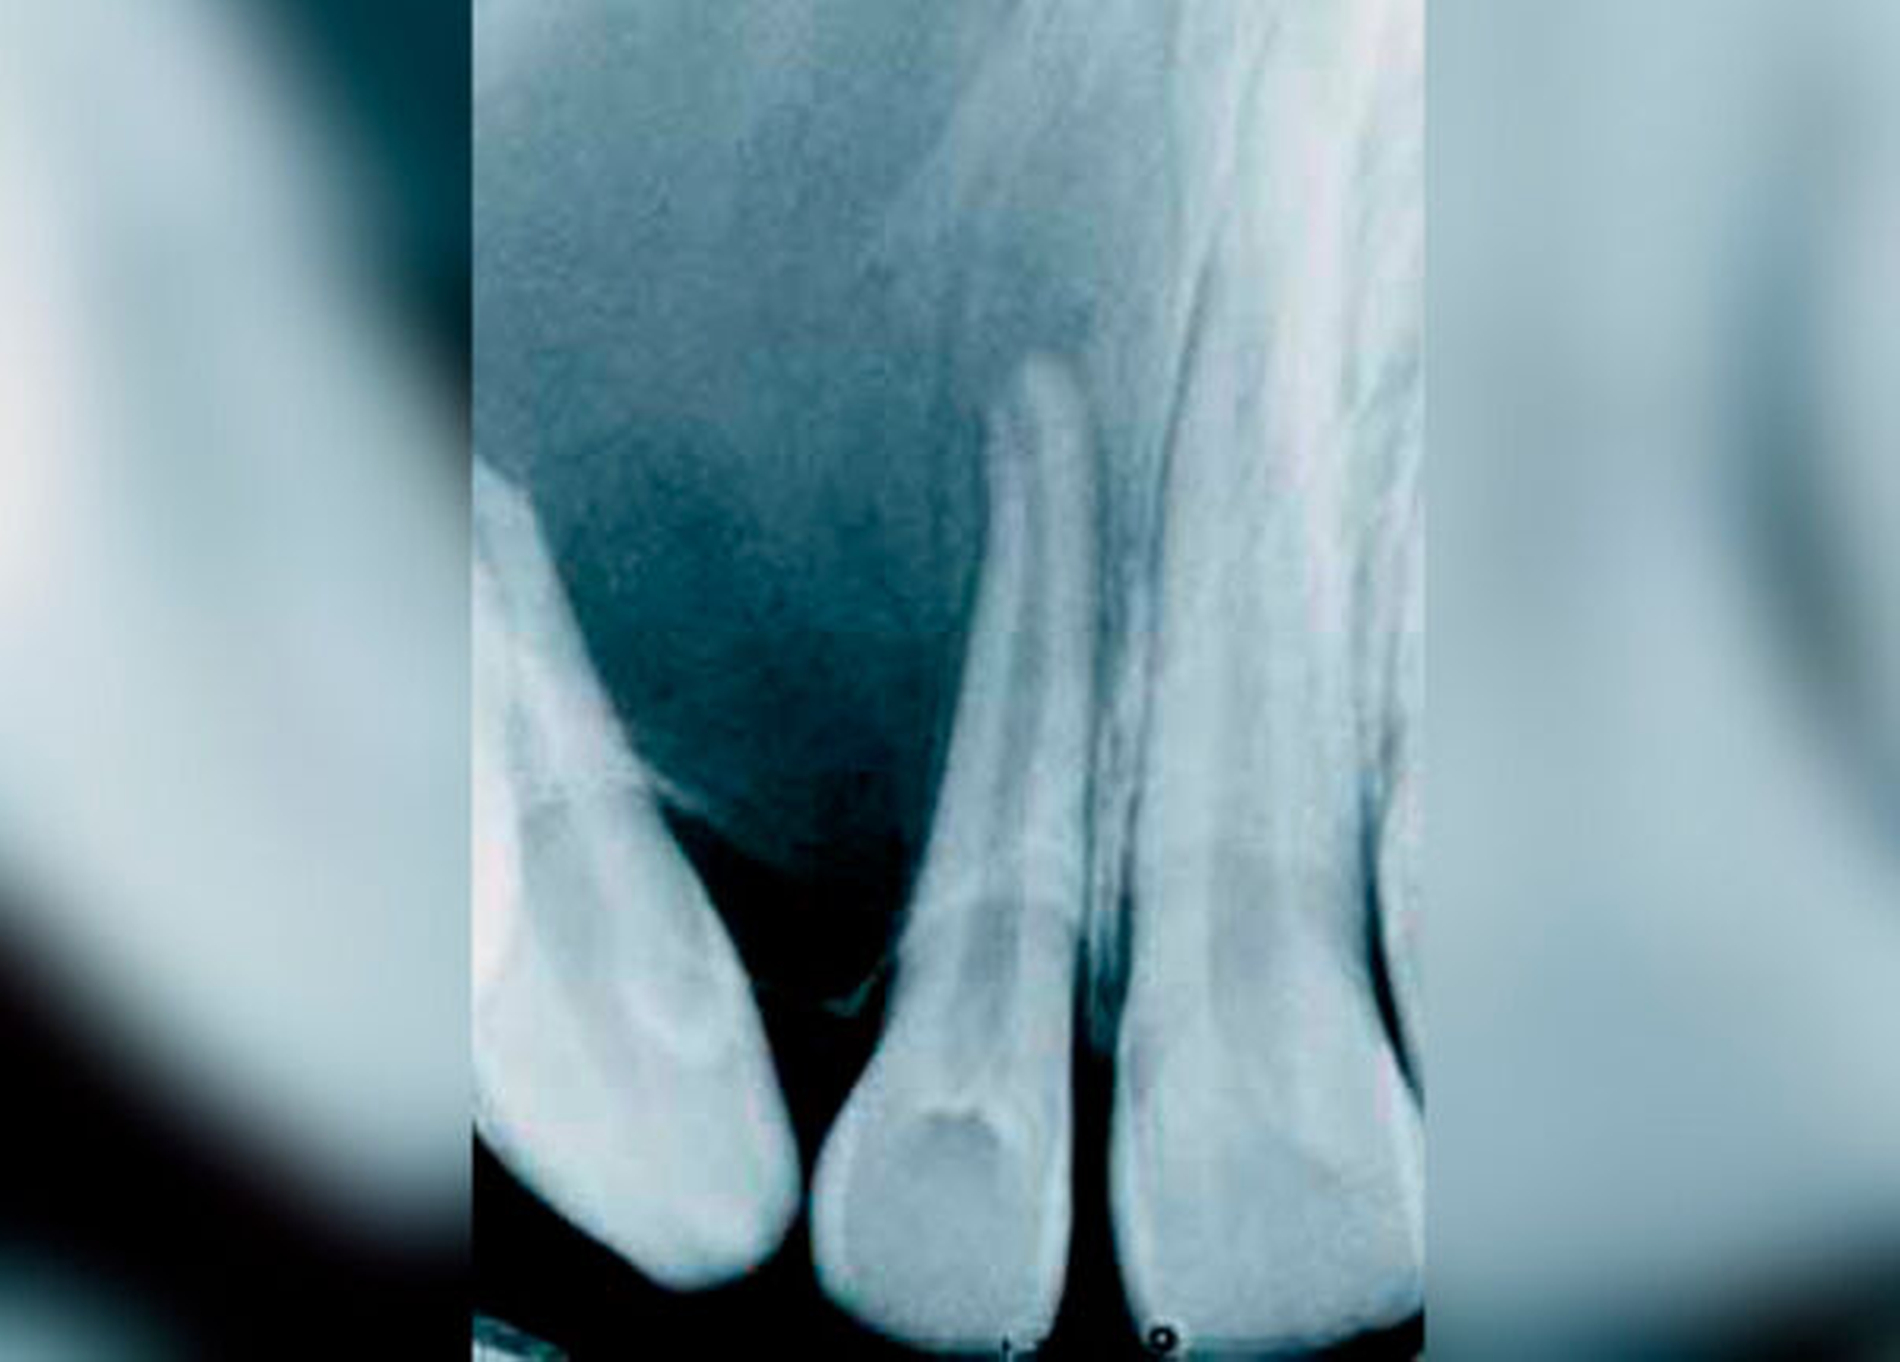

Die GZ wurde auch der parodontalen Zyste gegenübergestellt. Während letztere zwischen den Wurzeln sämtlicher Zähne entstehen kann, erscheint die GZ typischerweise nur zwischen dem lateralen Schneidezahn und dem Eckzahn, dort wo sich Prämaxilla und Maxilla vereinen. Es wurde Wert darauf gelegt, dass die Zyste zwischen parodontal und pulpal gesunden Zähnen vorkommt und somit ein Zweifel an ihrem fissuralen Ursprung ausgeschlossen ist. Die GZ verdrängt die Wurzeln des lateralen Incisivus und des Eckzahns, was als erstes klinisches Zeichen beschrieben wird. Später kann es zu einer Vorwölbung der vestibulären Schleimhaut kommen, oft assoziiert mit einem Druckgefühl (Abb. 1 bis 5).

Kurz darauf wurden neue Einteilungen von Kieferzysten publiziert [Roper-Hall, 1938; Roper-Hall, 1943]. Die GZ wurde nun innerhalb einer Gruppe von entwicklungsbedingten Zysten den fissuralen Zysten zugeordnet, gemeinsam mit den medianen (alveolären) Zysten. Die radiologische, klinische und histologische Beschreibung der GZ unterschied sich nur geringfügig von der Erstbeschreibung. Die radiologisch ovale, tropfenförmige Form wurde als typisches Zeichen nicht-odontogener Zysten bei vitalen Nachbarzähnen interpretiert. Zwischen 1937 und 1952 wurden zwölf Fälle in der Welt-Literatur beschrieben [Akira & Kitamura, 1952]. 1957 wurde erstmals über ein zentrales Fibrom berichtet, das sich auf dem Röntgenbild wie eine GZ darstellte [Nishimura et al., 1957].

wurde über den Fall eines 13-jährigen Mädchens mit einem adenomatoiden odontogenen Tumor berichtet, der als GZ hätte diagnostiziert werden können [Kuntz & Reichart, 1986]. Auf der Panoramaschichtaufnahme zeigte sich die typische, birnenförmige, gut abgrenzbare, homogene, unilokuläre Aufhellung zwischen dem lateralen Inzisivus und dem Eckzahn, deren Wurzeln divergierten. Die Nachbarzähne reagierten positiv auf den Sensibilitätstest, waren nicht erhöht beweglich, und die Patientin hatte keinerlei Beschwerden. Die Zyste wurde enukleiert; die Läsion reossifizierte vollständig. Die pathohistologische Untersuchung des (gesamten) entfernten Gewebes ergab die Diagnose eines adenomatoiden odontogenen Tumors [Kuntz & Reichart, 1986]. In der Literatur waren bis zu diesem Zeitpunkt fünf ähnliche Fälle eines adenomatoiden odontogenen Tumors bekannt, der eine GZ vortäuschte. Die betroffenen Patienten waren zwischen 13 und 20 Jahre alt [Fahim et al., 1969; Hermann, 1973; Khan et al., 1977; Glickmann et al., 1983]. Man kam zum Schluss, dass die Form der Aufhellung, die spezifische Lokalisation und der Effekt auf die Nachbarzähne nicht zur Diagnose GZ verleiten dürften [Kuntz & Reichart, 1986]. So genannte paradentale Zysten wurden 1976 [Craig, 1976] und 1983 [Stoneman & Worth, 1983] beschrieben. Diese Zysten waren mit teilweise oder vollständig eruptierten vitalen Zähnen ausschließlich im Unterkiefer assoziiert [Vedtofte & Holmstrup, 1989]. Für diese Zysten wurde der Begriff entzündliche paradentale Zyste (inflammatory paradental cyst = IPC) vorgeschlagen, um eine Verwechslung mit der entwicklungsbedingten lateralen Parodontalzyste (lateral periodontal cyst of developmental origin = DLPC) zu vermeiden. Beide Zysten sind an der lateralen Wurzeloberfläche zu finden. Bereits zuvor war beschrieben worden, dass DLPC in der „globulomaxillären“ Region vorkommen können [Christ, 1970; Wysocki, 1981; Vedtofte & Holmstrup, 1989]. Die IPC wurde hingegen bisher nur in der Mandibula im Zusammenhang mit teilweise oder vollständig eruptierten, vitalen Zähnen beschrieben [Craig, 1976; Stoneman & Worth, 1983].

Die klinische und pathohistologische Evidenz spricht überzeugend dafür, dass Zysten im „Globulomaxillären Bereich“ radikuläre Zysten, laterale Parodontalzysten, odontogene Keratozysten [Christ, 1970], kalzifizierende odontogene Zysten, adenomatoide odontogene Tumore [Rosenberg & Cruz, 1963; Giansanti et al., 1970; Khan et al., 1977], odontogene Myxome [Rud, 1964; Taicher & Azaz, 1977], Ameloblastome [Aisenberg & Inman, 1960], zentrale Riesenzellgranulome oder hämorrhagische Knochenzysten [Peters & Wassow, 1968] sind (Abb. 6 bis 13).